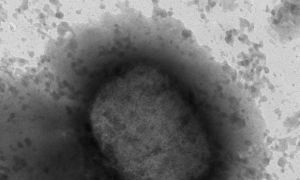

WHO cảnh báo lây nhiễm đậu mùa khỉ ở phụ nữ mang thai và trẻ em

Tổ chức Y tế thế giới (WHO) cảnh báo lây nhiễm đậu mùa khỉ ở nhóm nguy cơ cao, như phụ nữ mang thai, người suy giảm miễn dịch và trẻ em.